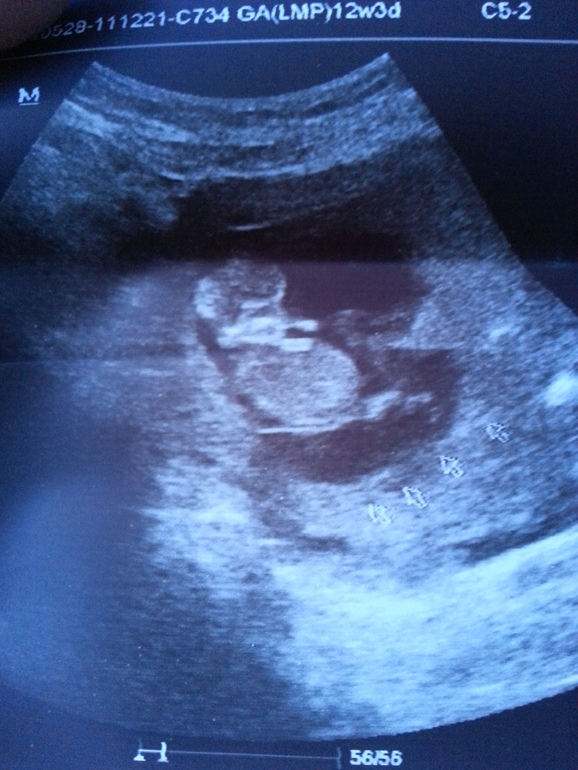

Сделала УЗИ.....Скрининг....

С моим маленьким все хорошо...

он такой у меня сладенький... Ручками шевелет, ножками шевелет

. Правда гематома не прошла...она увеличелась... теперь ее размеры 4,6×1,7. Теперь узи-контроль через каждые две недели... до тех пор пока я не начну чувствовать шевеление маленького...

КТР - 5,6 СМ

ТВП - 1.2 ММ

Вот он мой милаха)) 10 - 11 недель.